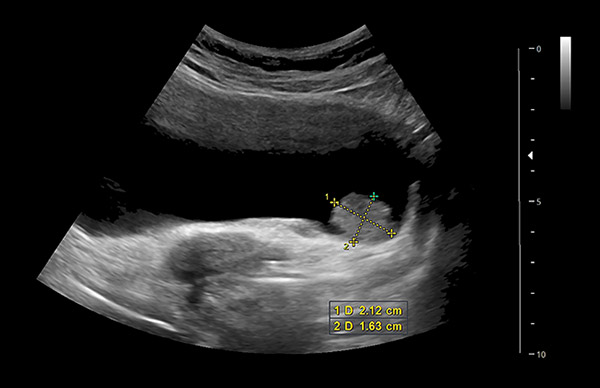

11. kép:

Hólyagtumor

Ezen a képen egy hugyhólyag falából kiinduló daganat látható. Itt egy karfiol szerű kinövés látható a hugyhólyag alsó falán, ami a képen a lemért képletnek felel meg.